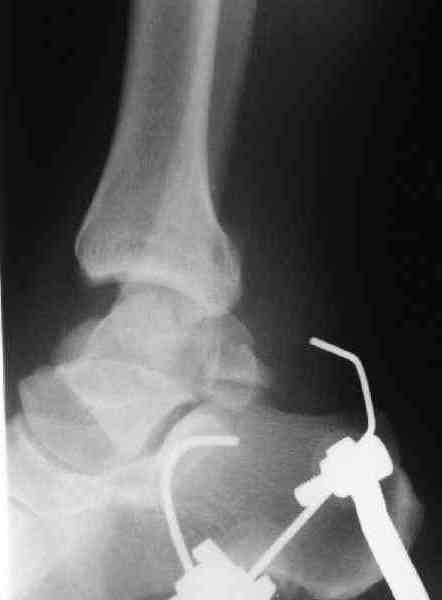

Interesting case

The ankle joint looks ruined. I wonder howcome is it as ruined after 2 days. I would open the joint( Some people would artroscope it) and judge the osteosynthes vs ankle fusion according to the ankle joint condition. The subtalar does not look injured, but if you feel there is a clinical

problem- CT it. Above all- when I see such an X-Ray I call the resident who ordered it and tell him that I would expect him first thing to reduce it on arrival since the soft tissue suffer and I hope that currently the p-nt is reduced to some extent at least.

Sorry- I revised it and the talus is fractured- take him to the theater at once and reduse it with Int Fix

The soft tissue will be a problem- Ex Fix will be better thn plaster

а основании двух видов ренгенограмм невозможно радикально решить о необходимости открытой репозиции или первичного артродеза.

Для оценки состояния нужны дополнительные исследования, например Canale или Broden ренгенограммы и Компьютерная томография.

При переломах тарана всегда имеется риск AVN, а классификация Hawkins поможет разобраться с предполагаемыми осложнениями.

Если в первом типе, когда перелом шейки без смещения, тогда AVN менее 10%, при втором типе когда имеется смещение и вывих тарана в субталарном сочленении меньше 40%, а при типе III когда смещение в голеностопном и субталарном суставах - около 90% и в типе IV, когда происходит полный вывих, риск AVN достигает 100%.